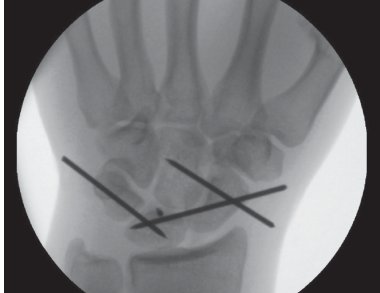

Quiz on Wrist Perilunate Dislocation 1. Describe this radiograph. Show Answer This is a lateral radiograph of…